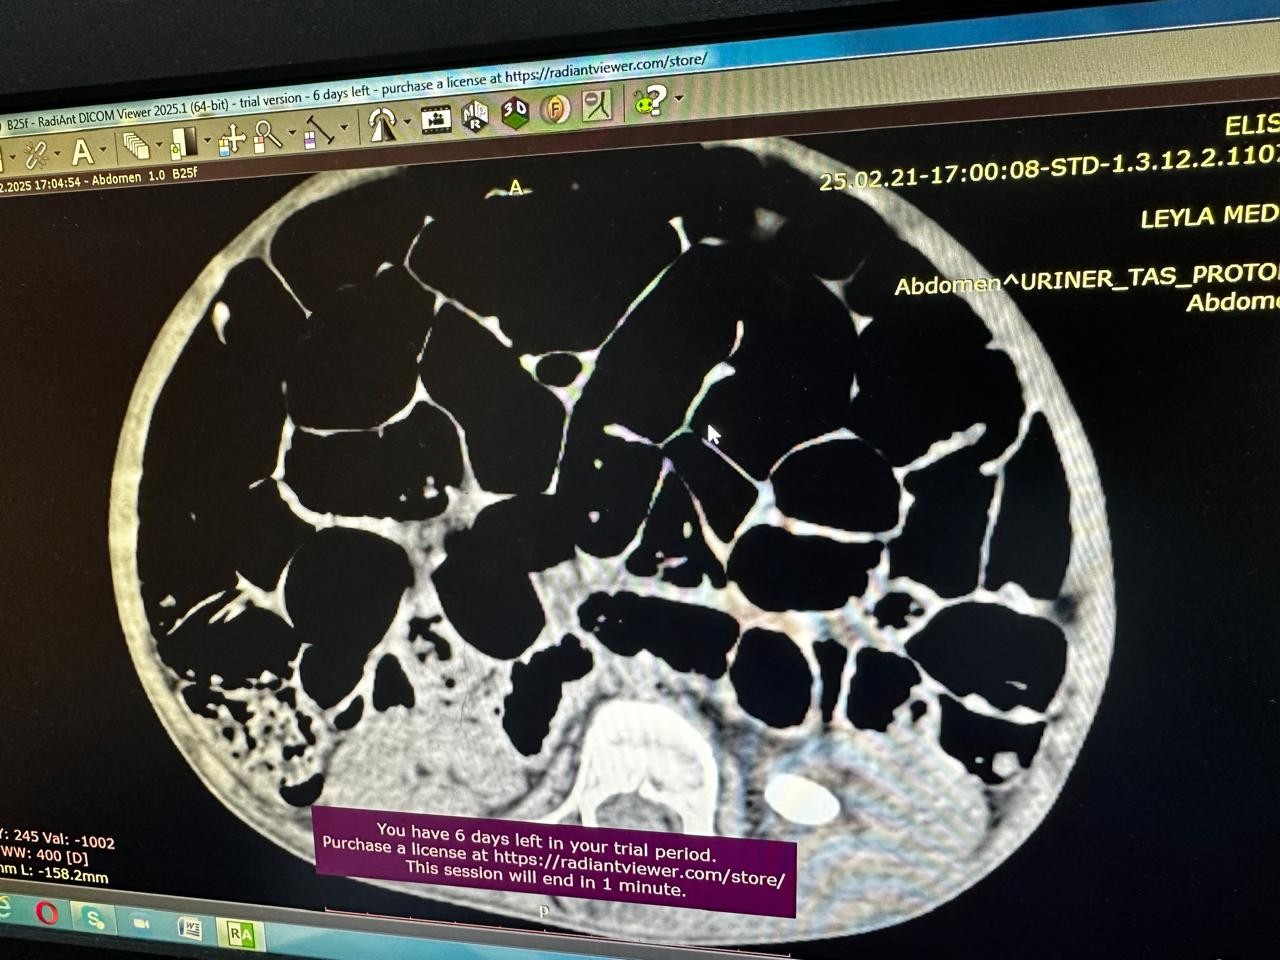

Əməliyyat zamanı xəstənin sol böyrəyindən mərcanvari daş xaric edilib.